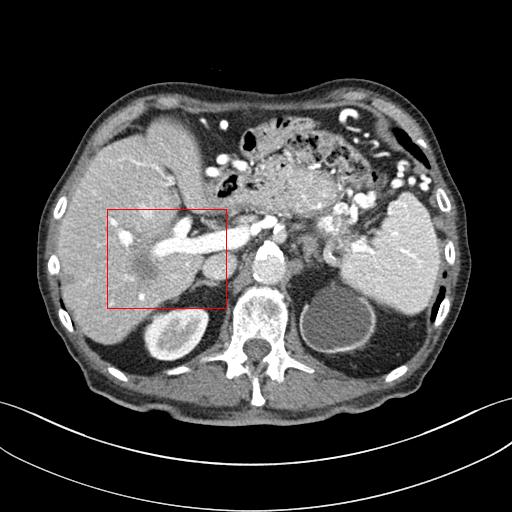

Figure 3: Comparison of denoising performance of different network. The boundary line of different organ extracted from the NDCT image is superimposed on other images. As seen, many pixels are missing around the boundary line in the output of M1

Figure 4: Zoomed version of the ROI taken from the images of Figure 3. In the zoomed version missing boundary pixel is clearly visible in the output of M1.

This section systemically investigates the efficacy of every module proposed in this study. We considered three different networks; first, baseline model(M1), where the inverting block is replaced with dense block, and trained using minimizing mean square distance between two noisy observations(i.e. fsubscript𝑓\mathcal{L}_{f}). Next, two independent baseline model(one for forward mapping, one for reverse mapping) is jointly trained using a linear combination fsubscript𝑓\mathcal{L}_{f}, and rsubscript𝑟\mathcal{L}_{r}, similar to cycle consistent network paradigm. The forward mapping network is used for testing. We refer this model as M2. In both M1, and M2, we increased the depth of the network to make the representation power of these networks comparable with inverting network. Finally, the proposed method, referred as M3. Table 2 depicts the objective evaluation of the three networks using the D1 dataset. Both M2 and M3 use reverse mapping to regularize the network; the influence of the same in the denoising performance is evident from Table 2. Adding cycle consistency loss has improved the performance of the same baseline model significantly. The inverting network performed considerably better than the network M2. It improves PSNR by 0.23dB. As discussed in the above section, in case cycle consistency loss, an additional network is trained, but that does not always guarantee invertibility, whereas inverting network architecture inherently possesses reversibility, which acts as a strong regularizer. In Figure 3 we have shown denoising performance of different networks visually. To demonstrate the requirement of regularization, we first extract the boundary line of the various organ from the NDCT image and superimpose the boundary line on the output of different networks. As shown in Figure 3, many pixels around the boundary line of M1 network output are missing. Using the reverse mapping, the issue of the end-organ missing pixel is successfully overcome in M2 and M3. The granular pattern is also less present in the M3 than M2. The zoomed version of a ROI taken from the images of Figure 3 is given in Figure 4 for better perception. In Figure 5 we give an example of the performance of the invertible network in reverse mapping. Here, the predicted LDCT image is produced by using the predicted clean image of the forward mapping as the input for reverse mapping. As shown, the predicted noisy pattern is similar to the original noise pattern. The same streaking artifacts are present in both the noise pattern; also, the noise variance is different in the various spatial region depending on the signal intensity of the original CT image. It validates that the loss of information in reverse mapping is minimal. Due to the invertible network’s structural advantage, the network also preserves every information present in the input image in the forward mapping.